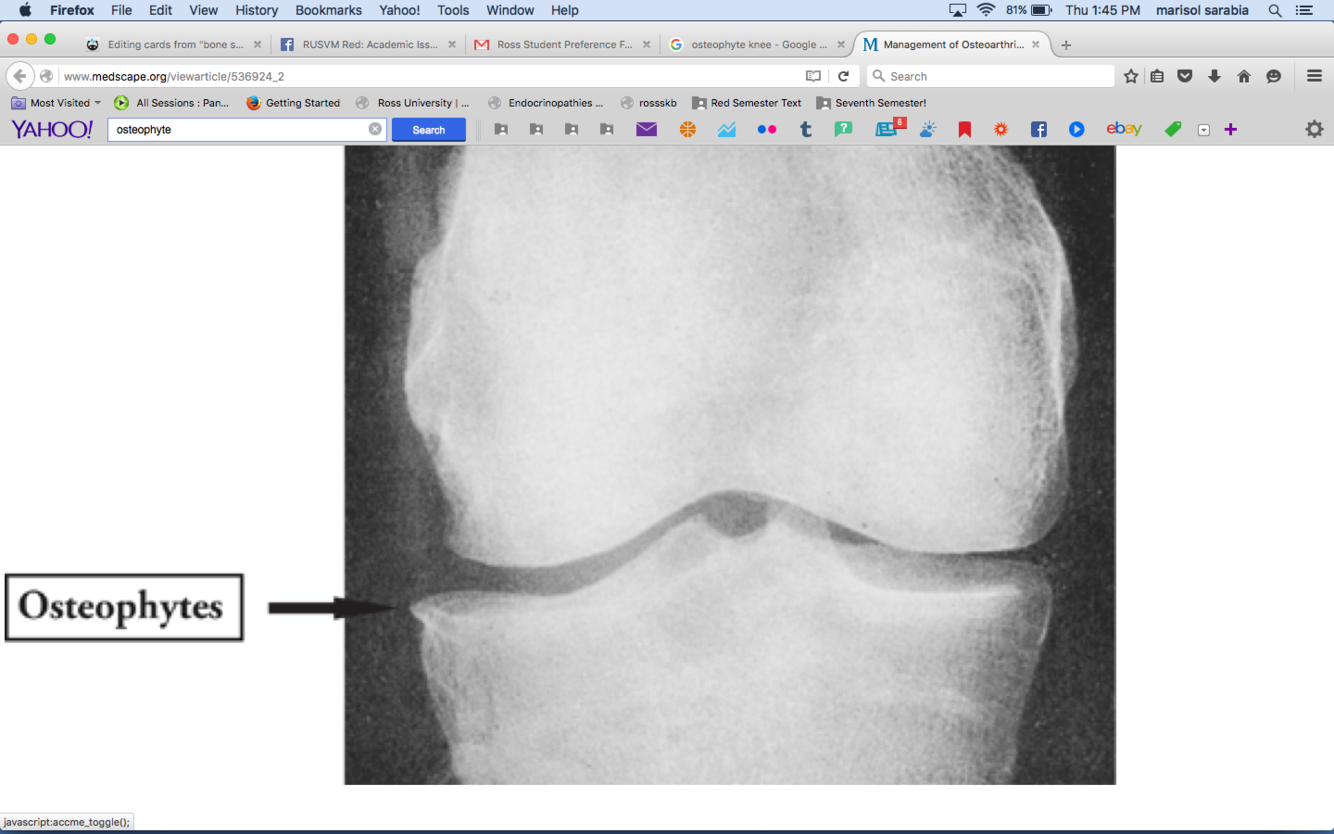

what type of formation may we see with bone spavin

significant osteophytes formation

what is this a pix of

DJD of distal intertasrsal and tarso metatarsal jts